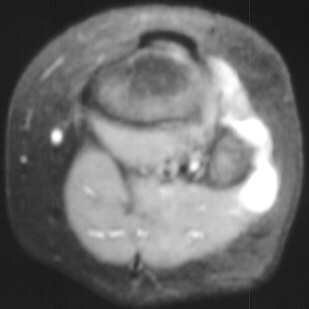

XRAY EVALUATION:

Radiographic examination of the left knee revealed no osseous abnormalities . A fullness of the soft tissues was evident over the fibular head. MRI examination of the left knee displayed a 2 cm. by 0.8 cm. lobulated mass in the region of the common peroneal nerve with no enhancement . On the T-2 weighted sequences there was abnormal increased signal of the tibialis anterior, extensor digitorum longus and peroneus longus muscle bellies suggesting atrophy . EMG/NCS were performed which clearly documented electrodiagnostic evidence of a severe peroneal neuropathy distal to the take-off of the nerve to the short head of the biceps.